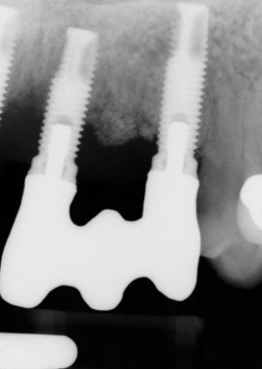

Radiographs

Given patient concerns about radiation exposure, it is important to know how, when, and why radiographs should be taken. Although there are concerns about radiation, radiographs make it possible to determine bone levels at baseline—ie, at implant and restoration insertion—and to monitor them over time. Vertical radiographs should be as parallel as possible to the implant body, so that the implant threads are clearly visible. Typically, periapicals should be taken once a year around dental implants. Figure 3 and Figure 4 shows bone loss up to the fifth and sixth thread.

Radiographs showing bone loss around an implant.

Figure 3

Figure 4